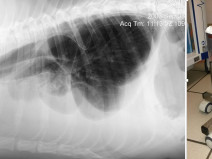

• Après-midi Travaux pratiques de radiographie / TP1 Le Thorax

Le GEIM vous propose une séance de travaux pratiques de radiographies sur le thorax. Tous les aspects sont abordés sous la forme de TP de lecture de radiographies numériques sur station de travail Osirix sur Mac (3 vétérinaires maximum/ordinateur).